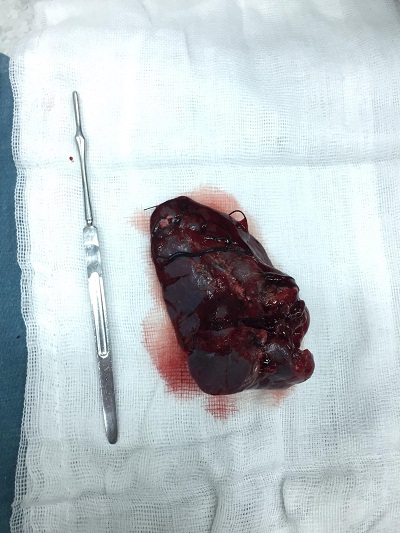

Trong quá trình phẫu thuật, quan sát thấy rất nhiều máu cục khắp bụng, nhiều máu loãng không đông. Thám sát thấy lách vỡ cực dưới gần hoàn toàn, đang chảy máu. Sau khi xin ý kiến BS Tạ Vũ Quỳnh- Trưởng khoa Ngoại tổng quát. Ê kip trực BS Trần Việt Hoàng – BS Võ Quang Huy quyết định cắt lách toàn phần.

Lách vỡ hoàn toàn